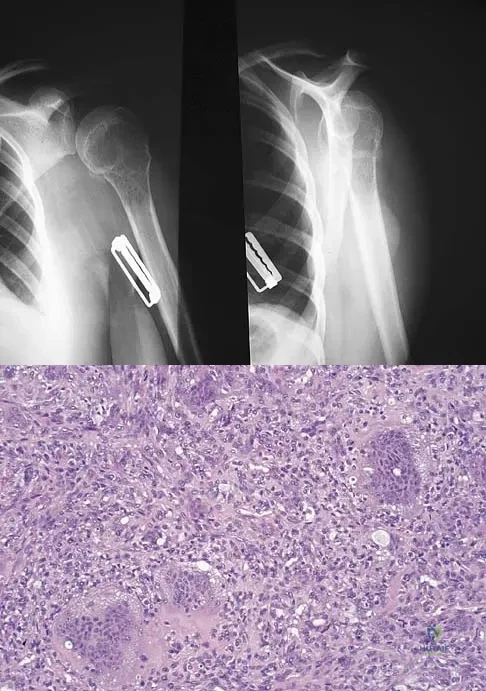

A 34-year-old woman reports constant midlateral arm pain after sustaining minimal trauma to the shoulder. Radiographs and a biopsy specimen are shown in Figures 29a and 29b. What is the most likely diagnosis?

Explanation